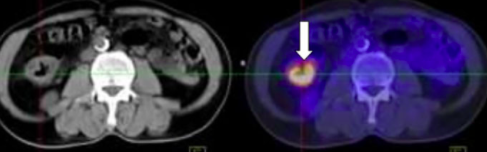

Hình ảnh khối u đại tràng phải, kích thước 3x4cm của bệnh nhân H.